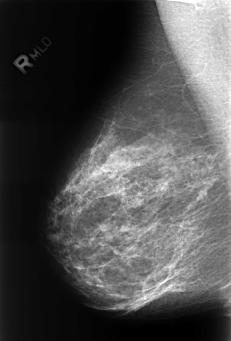

Volume: benign_without_callback_01 Case: B-3245-1

B_3245_1.RIGHT_MLO

filename B-3245-1

DATE_OF_STUDY 11 8 1998

PATIENT_AGE 48

DENSITY 2

RIGHT_MLO LINES 4432 PIXELS_PER_LINE 2992 BITS_PER_PIXEL 12 RESOLUTION 50 NON_OVERLAY